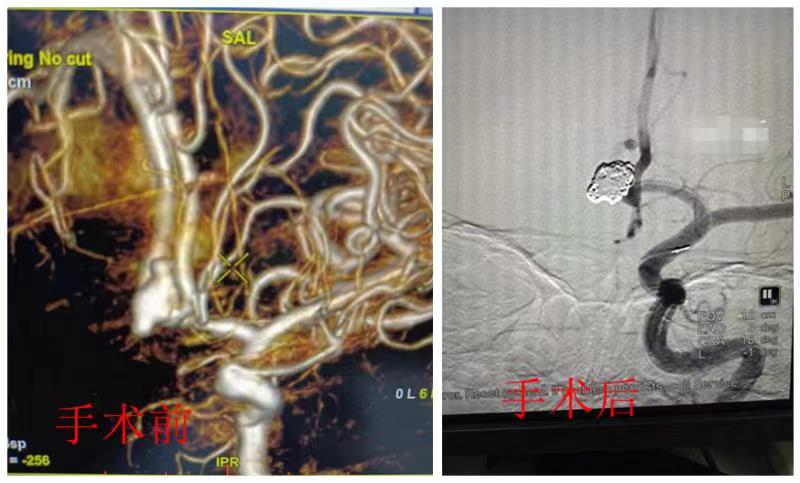

当即送介入室为患者行主动脉造影术+全脑血管造影术,术中清晰大小约12*8mm的前交通动脉瘤。情况十分紧急,与家属沟通后,需要立即行颅内动脉瘤栓塞术。

颅内动脉瘤栓塞术全程需要在血管内完成,颅内大血管直径约为1.5-6毫米,对手术医生技术要求较高。在上级医院专家的精心指导下,通过麻醉科、介入室的密切配合,神经外科专家彭卫华成功将5枚弹簧圈填塞瘤腔,复查造影动脉瘤未见显影。手术过程顺利、切口仅有米粒大小,创伤小、出血少、恢复快。